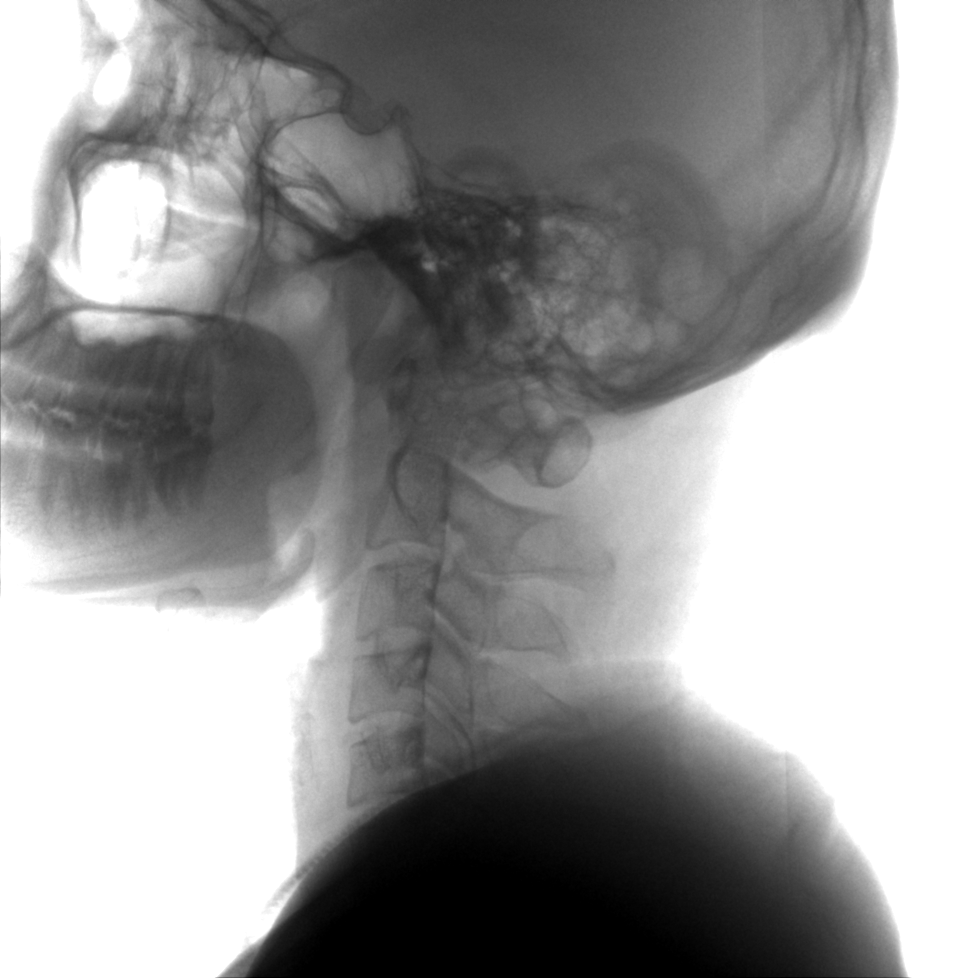

成像清晰、操作簡(jiǎn)易、擺位便捷,主要適用于骨科、脊柱外科、矯形外科、創(chuàng)傷骨科及手術(shù)室等,能大幅度提升手術(shù)水準(zhǔn),降低手術(shù)風(fēng)險(xiǎn)和并發(fā)癥的概率。

術(shù)中三維成像和橫斷面圖像提供多角度的手術(shù)診斷信息,輔助醫(yī)生進(jìn)行術(shù)中評(píng)估判斷,諸如骨折復(fù)位情況和內(nèi)植入螺釘?shù)某叽绾臀恢?,輔助手術(shù)更好地完成。

提供更大的術(shù)中三維成像視野,采集更多圖像信息,可一次拍全全段頸椎、全段腰椎、七節(jié)胸椎、雙側(cè)骶髂關(guān)節(jié)、股骨頭及單側(cè)盆骨。